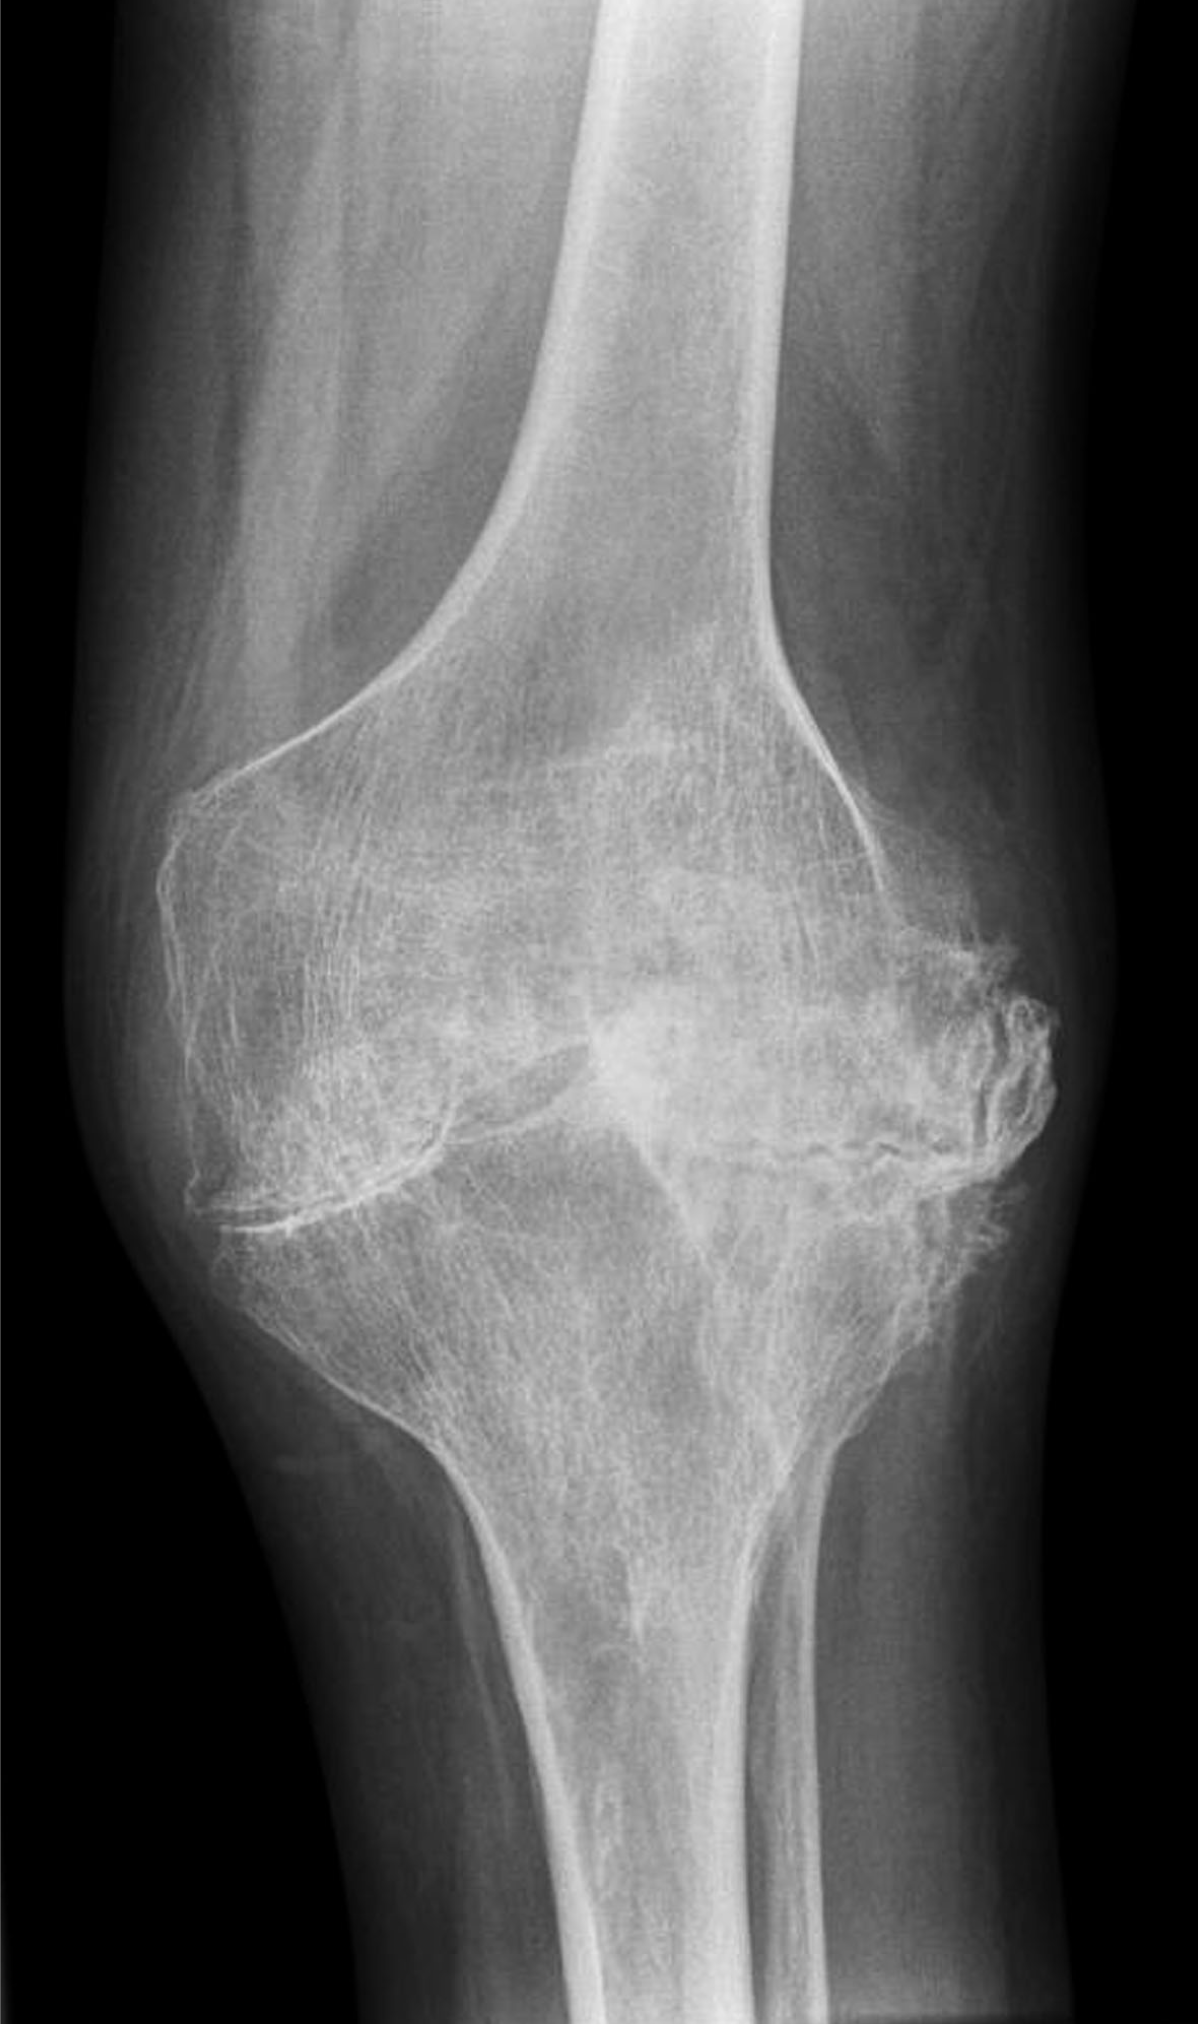

A 34-year-old male with hemophilia A presented to the emergency department with pain and swelling in his left knee following a minor fall. He was known to suffer from advanced arthropathy and was awaiting a total knee replacement. On clinical examination, the left knee was swollen and tender with a reduced range of movement. Plain radiograph (antero-posterior and lateral views) performed (Figure 1) (Figure 2)excluded a fracture or dislocation but demonstrated classic appearances of hemophilic arthropathy with severe secondary degenerative changes. He was discharged with adequate simple analgesia and outpatient follow-up appointments with his hematologist and physiotherapist.

Figure 1: Anteroposterior radiograph of the knee showing widened intercondylar notch, bulbous femoral condyles, flattened condylar surfaces, periarticular osteoporosis, marked loss of articular cartilage, sclerosis, and osseous proliferation.

Hemophilia is an inherited, X-linked recessive disorder caused by deficiency of plasma clotting factors VIII, IX or XI. It manifests in males while females are asymptomatic carriers. Hemophilic arthropathy results from repeated episodes of hemarthrosis, blood within the joint damages the articular cartilage directly. [1] Large joints (knee, ankle, elbow, and shoulder) are usually affected. The classic appearance of hemophilic arthropathy in the knee is shown in Figures 1 and 2, i.e., widened intercondylar notch, bulbous femoral condyles, flattened condylar surfaces and squared inferior margin of the patella. [2] Due to repeated episodes of hemarthrosis, our patient also had severe secondary osteoarthritic changes with near-total joint space loss. Hemophilic arthropathy most often begins in the first or second decade of life and bleeding episodes tend to recur in the same joint with gradual progression to joint destruction. Recurrent hemarthrosis inevitably leads to synovial hyperplasia, subchondral resorption, erosions, articular cartilage destruction, joint space narrowing, and osseous proliferation. Periarticular osteoporosis and epiphyseal overgrowth occurs due to associated joint hyperemia. Clinical presentation varies according to disease severity with pain and joint swelling during acute episodes of hemarthrosis and progressive loss of joint function in longstanding cases. Prophylactic replacement of deficient clotting factors in the first or second decade of life may prevent or delay joint destruction in children with severe hemophilia. [3] Patients who present with an acute bleeding episode require adequate pain relief, prompt administration of deficient clotting factor and rest. Patients who suffer from repeated hemarthrosis despite optimal conservative management may benefit from synovectomy. Patients with end stage disease may require surgical arthrodesis or total joint replacement to control pain and restore some function as planned for our patient.